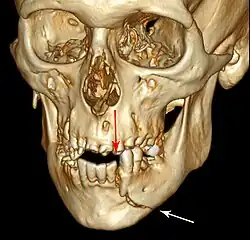

Injuries to supporting bone

This injury involves the alveolar bone and may extend beyond the alveolus.[5][6] There are five different types of alveolar fractures:

Trauma injuries involving the alveolus can be complicated as it does not happen in isolation, very often presents along with other types of tooth tissue injuries.

Signs of dentoalveolar fracture:

- Change to occlusion

- Multiple teeth moving together as a segment and are normally displaced

- Bruising of attached gingivae

- Gingivae across the fracture line often lacerated

Investigation: Require more than one radiographic view to identify the fracture line.

Treatment: Reposition displaced teeth under local anaesthetic and stabilise the mobile segment with a splint for 4 weeks, suture any soft tissue lacerations.